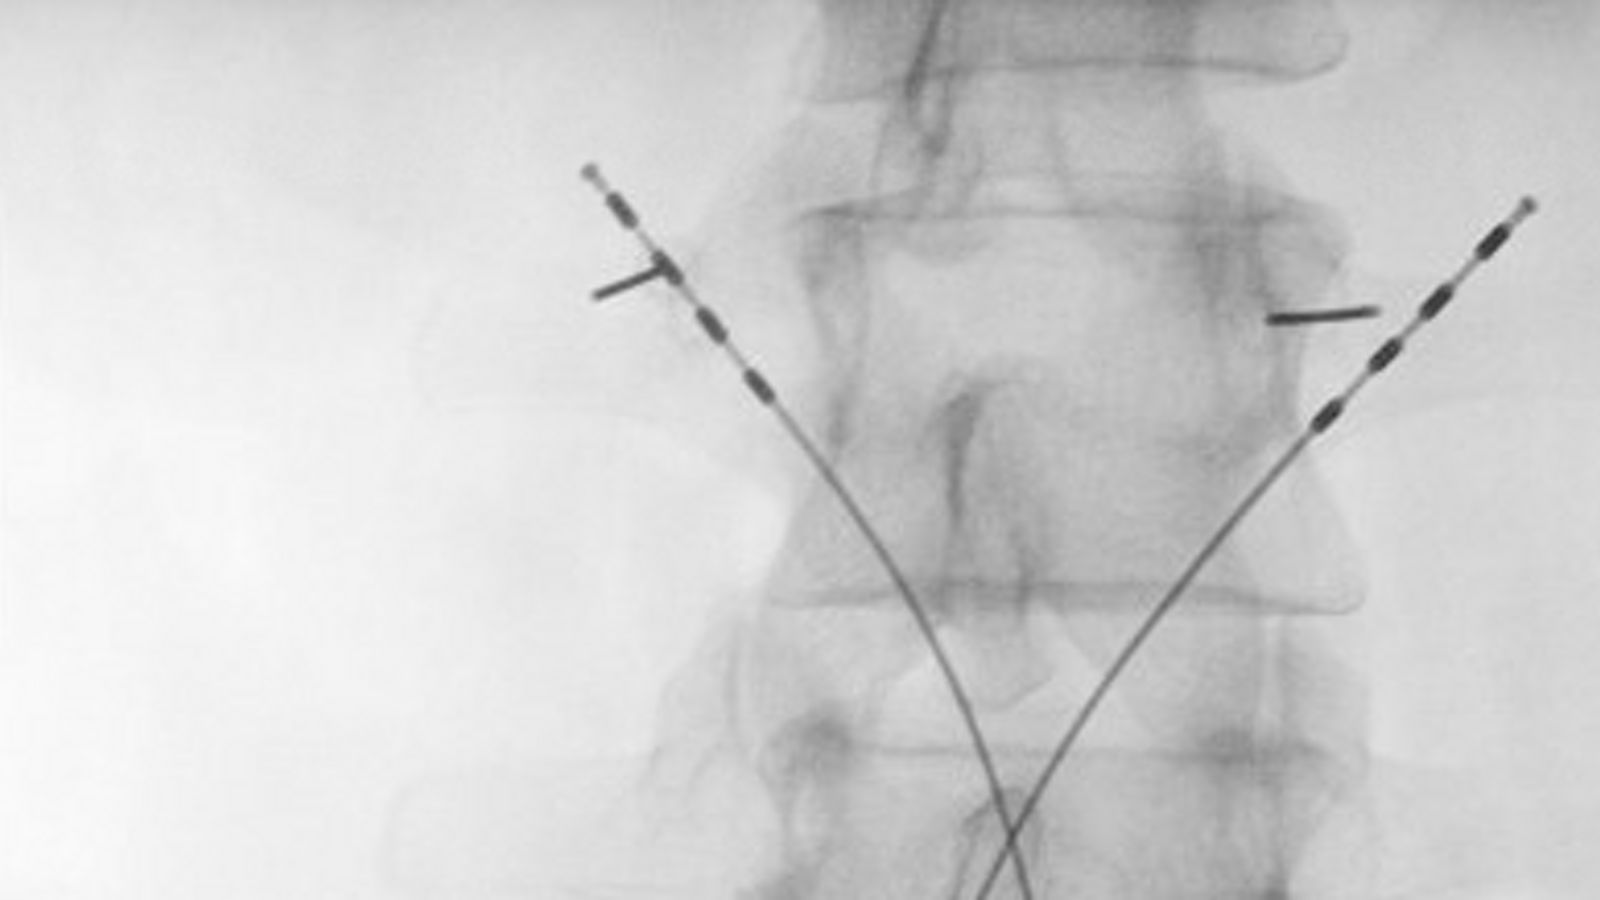

„Wenn herkömmliche Therapien gegen Schmerzen nicht helfen, kann die Neurostimulation viel bewirken“, erklärt Eichenauer. Das minimalinvasive Verfahren reaktiviert den tiefen Rückenstreckermuskel, der bei vielen Betroffenen nach einem einmaligen Schmerzereignis dauerhaft gehemmt ist. Über Elektroden, die neben der Wirbelsäule platziert werden, gibt der Neurostimulator gezielte elektrische Impulse ab und stellt die stabilisierende Funktion des Muskels wieder her.

Implantiert wird das System in einem kurzen Eingriff unter Vollnarkose. Das Steuergerät wird im unteren Rücken platziert und über zwei Elektroden mit dem betroffenen Bereich verbunden. Die tägliche Anwendung steuern die Patientinnen und Patienten selbst, meist morgens und abends für rund 30 Minuten.